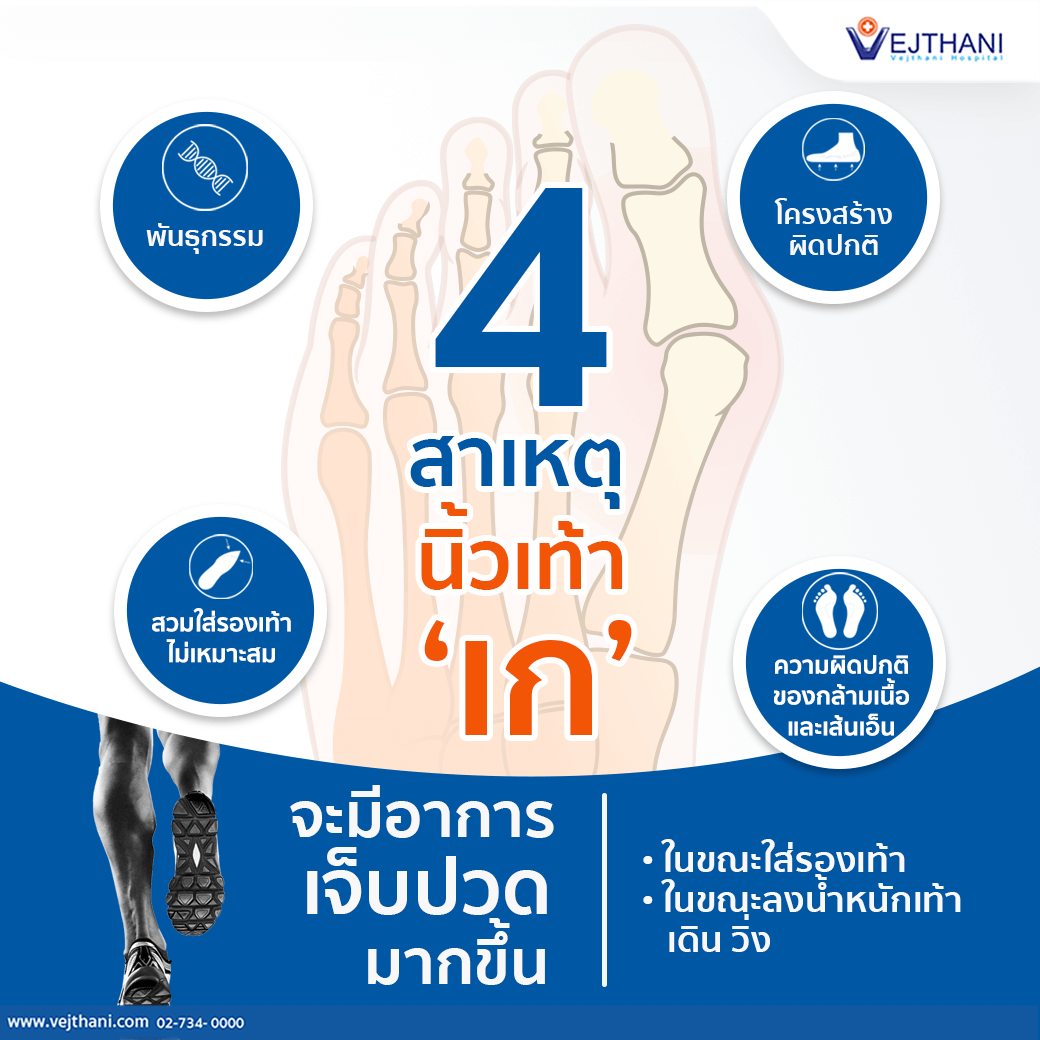

Facebook นิ้วเท้าเกผิดรูป โรคที่มาพร้อมกับความสวย – โรงพยาบาลเวชธานี

นิ้วเท้าเกผิดรูป โรคที่มาพร้อมกับความสวย – โรงพยาบาลเวชธานี รูปภาพประกอบอวัยวะเท้า PNG , เท้าอวัยวะของมนุษย์, เท้าใหญ่หนึ่งคู่ …

โครงกระดูกมือวาดไฟล์โปร่งใส | PNG Play 4 สาเหตุ “นิ้วเท้าเก” – โรงพยาบาลเวชธานี

4 สาเหตุ “นิ้วเท้าเก” – โรงพยาบาลเวชธานี 5 สาเหตุเกิด “กระดูกงอก” – โรงพยาบาลเวชธานี